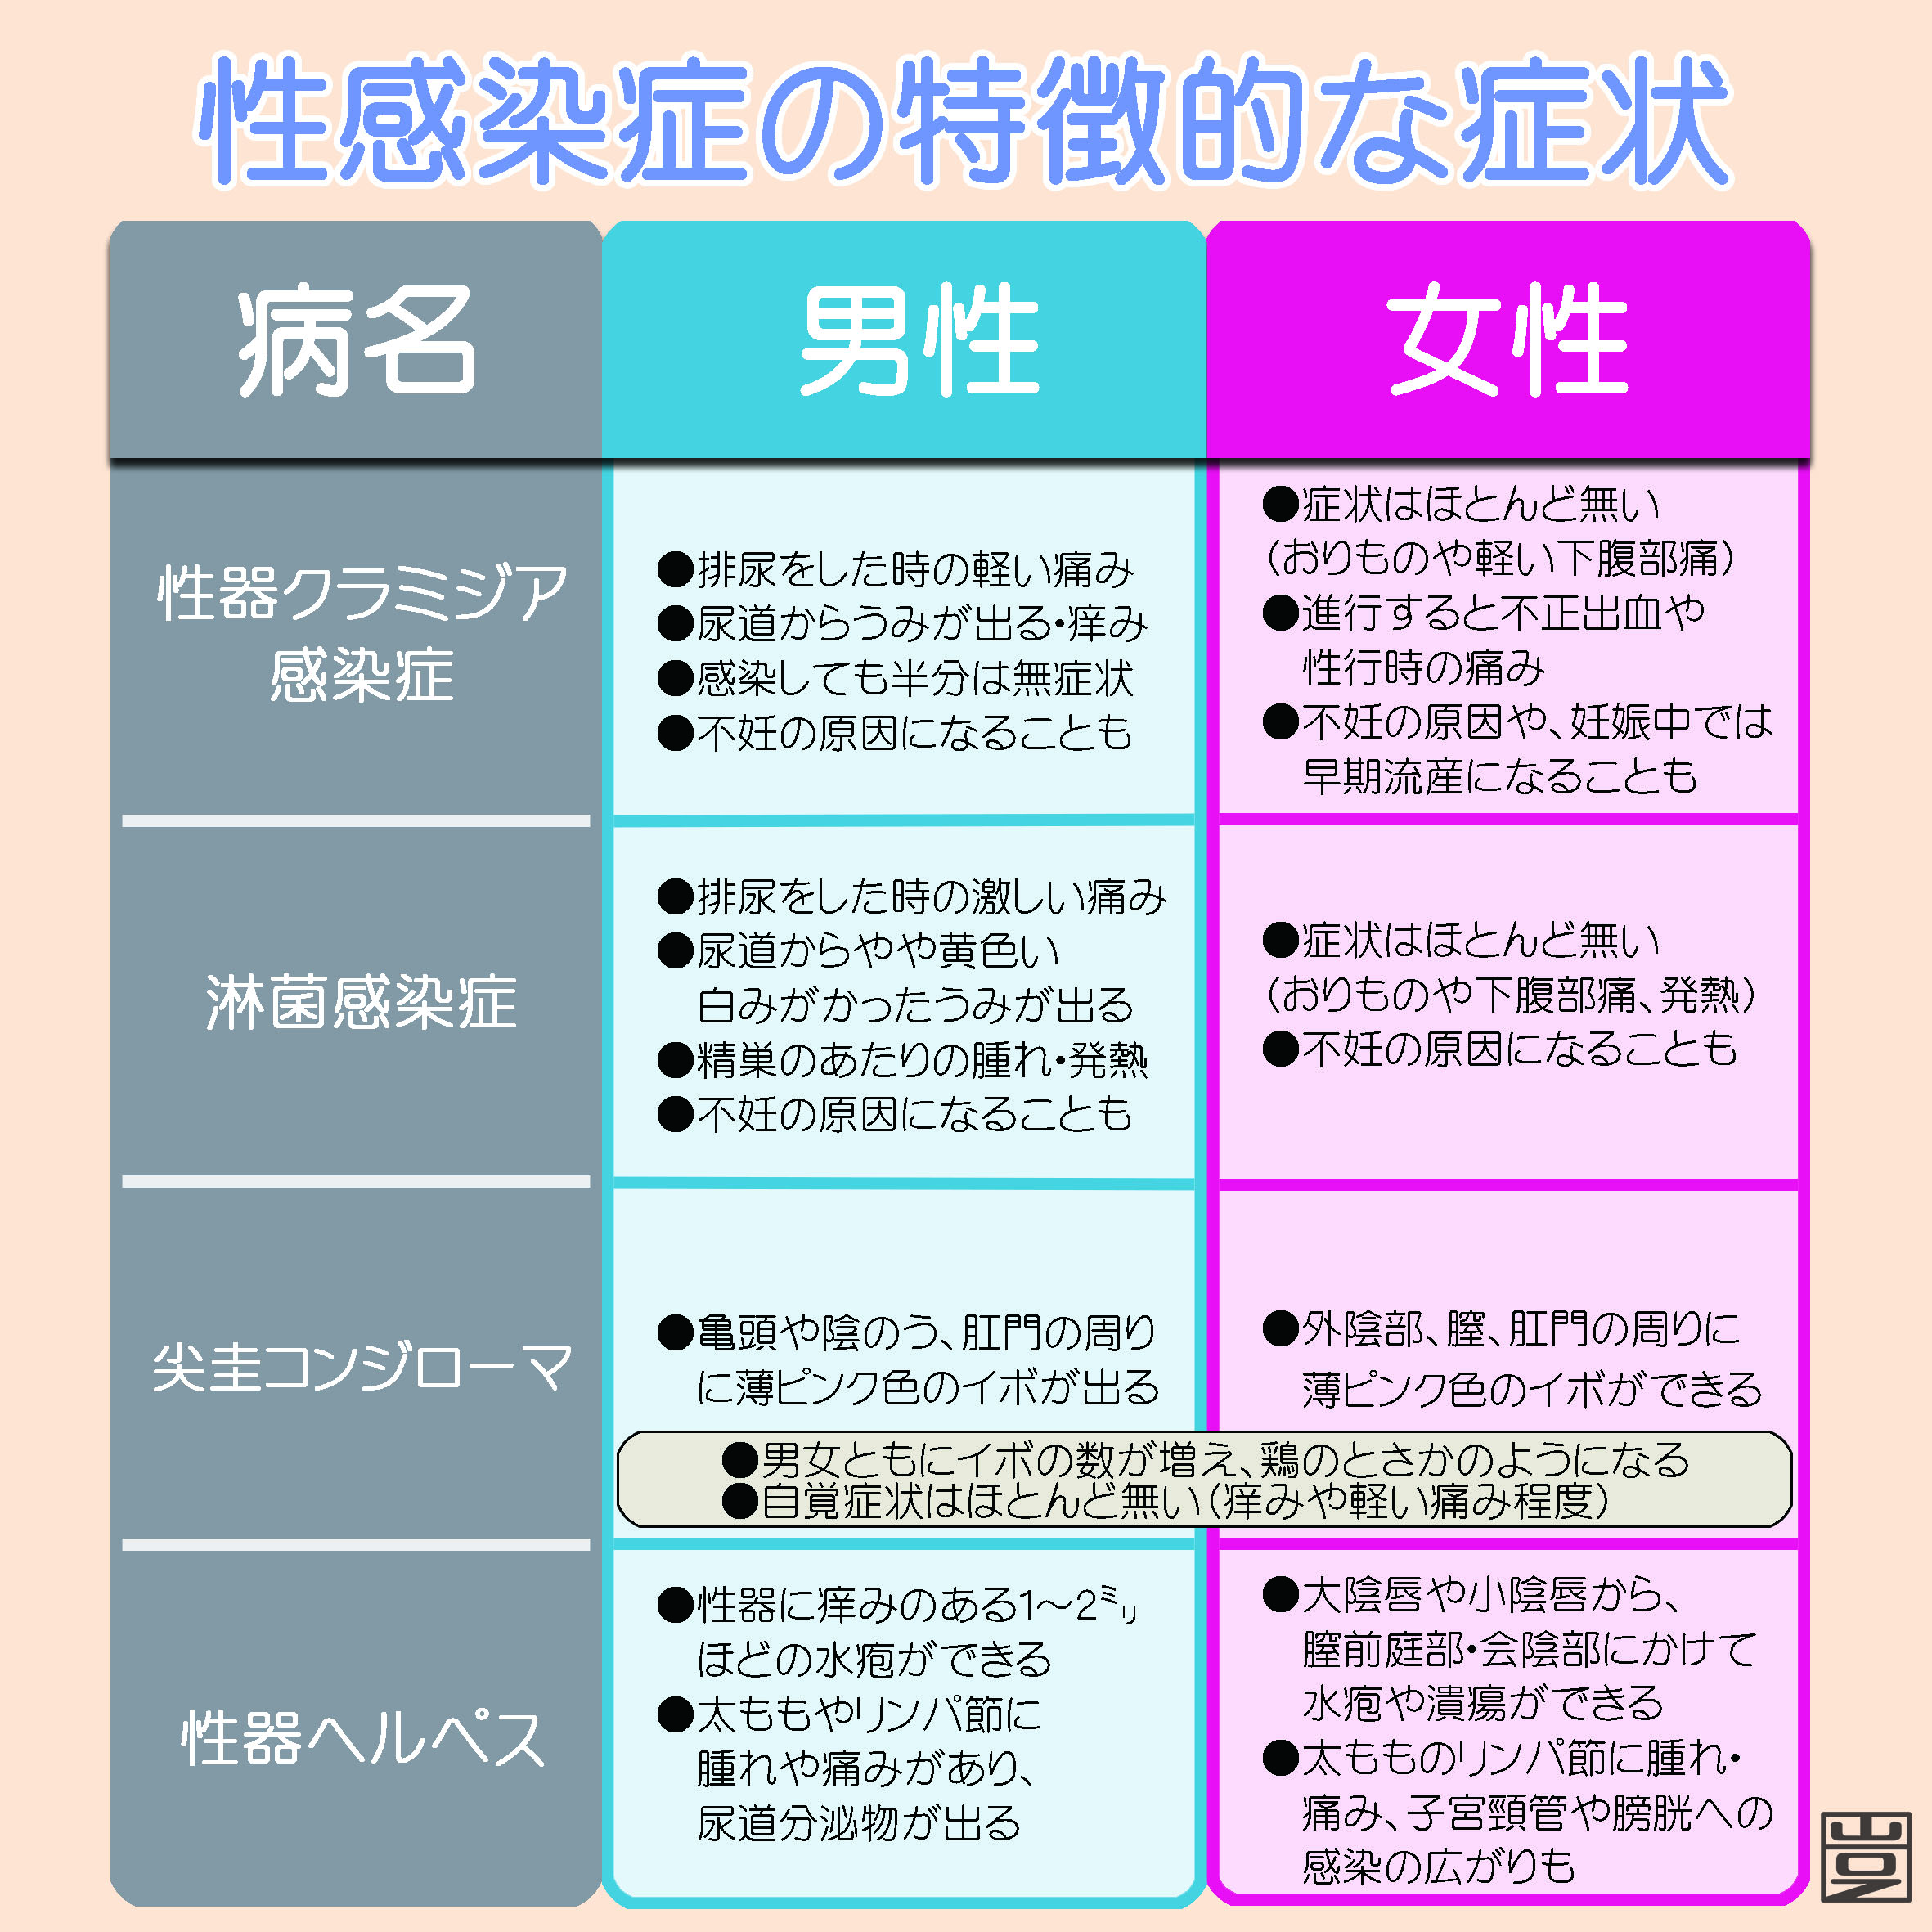

会陰 ( えいん )とは、 解剖学 において、狭義では 外陰部 と 肛門 の間、広義では左右の 大腿 と 臀部 で囲まれる 骨盤 の出口全体をさす。 恥骨結合 と左右の 坐骨結節 、 尾骨 を結ぶ菱形部となる。会陰と残尿感の解消には、 一体どのような関係性があるのでしょうか。 男性は蟻の門渡りを押すことで残尿感を解消できるのか? 排尿を終えた直後なのに「まだ膀胱内に尿が残っているような気がする、 なんだかスッキリしない」という不快感を覚える 男性の陰部のかゆみの原因として考えられる疾患とは? 男性の陰部にかゆみの症状があるとき、大まかな原因としては「性感染症」「皮膚疾患」の2つの場合が考えられます。 かゆみのある性感染症としては「性器ヘルペス・尖圭コンジローマ・梅毒」などがあり、どれも性行為により感染する可能性があります。 性器ヘルペスでは、陰部に水膨れができ